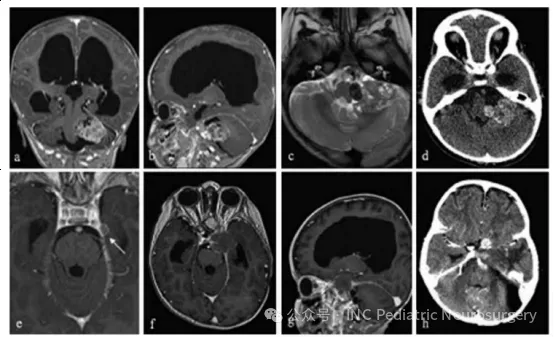

患者于2015年就诊,14个月大,主诉巨头畸形(macrocephaly)2个月、中央性肌张力低下、声音虚弱、吞咽困难,以及发育倒退。检查发现显著交通性脑积水与巨脑症,并伴有左侧小脑桥脑角(CPA)巨大异质性强化病灶,影像上可见出血伪影(blooming artifact)、液-液平面(fluid-fluid levels),并压迫脑干(图6)。

患者接受左侧后乙状窦开颅术(retrosigmoid craniectomy)。术中病理提示淋巴样细胞,术中仅能行次全切除(subtotal resection),脑干部仍有残留肿瘤。术后,患者持续存在颅神经功能缺损、吞咽困难(需行胃造口术),以及原因不明的交通性脑积水(需行脑室-腹腔分流术)。

最终固定病理结果显示非典型脊索瘤(atypical chordoma),免疫组化Brachyury、pan-CK、EMA、INl1基因产物(BAF47/INl1)均为阳性。在已报道的儿童脊索瘤病例中,她是年龄最小的患者之一,也是唯一发生在CPA的病例。

由于患儿年龄极小、肿瘤位置特殊且病理为非典型,治疗决策由多学科团队(MDT)制定。她接受了3个周期ICE化疗。虽然术后临床情况相对稳定,但随访影像显示手术部位病灶影像学进展,同时在左侧颞叶凸面出现新的硬膜基底结节性强化灶,考虑可能为脑膜播散。

此时,她接受3个月常规放疗,并对左侧CPA区域实施伽马刀强化照射。遗憾的是,肿瘤在放疗期间继续进展,MRI显示肿瘤向侧方侵入Meckel腔,并向左小脑幕后方延伸。

全外显子测序显示SMARCA4突变,随后开始Vorinostat+顺-维甲酸(cis-retinoic acid)化疗。尽管采取了积极治疗,肿瘤仍快速进展,累及左侧海绵窦、眶区及颅中窝。患者在短期姑息治疗后去世,距首次诊断约1年。

图6.患者10的左桥小脑角区脊索瘤影像学随访资料。(a)术前轴位T1加权钆增强MRI;(b)术前矢状位T1加权钆增强MRI;(c)术前轴位T2加权MRI;(d)术前轴位CT扫描;(e)术后5个月轴位T1加权钆增强MRI,显示左颞部新发硬膜病变(箭头);(f)术后9个月轴位T1加权钆增强MRI;(g)术后9个月矢状位T1加权钆增强MRI;(h)术后12个月轴位CT扫描。